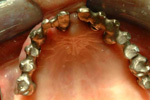

Protesi fissa completamente ancorato ad impianti in arcata superiori e riabilitazione parziale su impianti nei settori posteriori ed anteriori

CASO INIZIALE